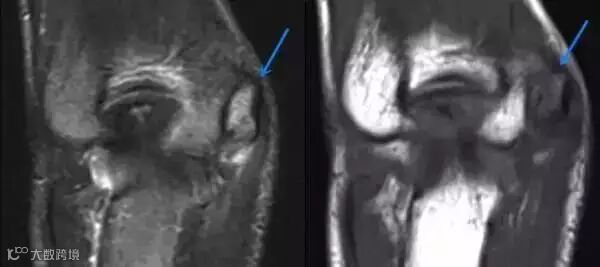

MRI:肱骨内上髁可见长T1长T2信号,骨骺板增宽。

3.病史和体格检查对诊断很关键,损伤的时间和机理,疼痛的部位、症状为诊断的关键因素。平片上肱骨内上髁炎表现为一系列征象:肱骨内上髁透亮线、分离或硬化,骨骺板增宽。MRI肱骨内上髁可见长T1长T2信号影,骨骺板增宽,有时同时可见屈肌总腱的T2信号增高。